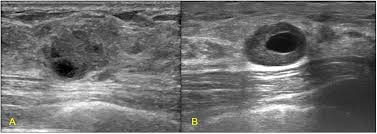

They can also occur in postmenopausal women taking hormone therapy. If the cyst comes back it may be evaluated again with mammogram and ultrasound and it can be drained again. On ultrasound a complex breast cyst will basically be treated in terms of internal echoes presence or absence of posterior enhancement thin septations and a thickened or irregular wall.

The cyst can be then be drained with a fine needle. For simple cysts no treatment is needed unless the cyst is especially large uncomfortable or painful. But the results of the ultrasound can influence the strategy for follow-up evaluation or treatment.

Breast cysts do not require treatment unless a cyst is large and painful or otherwise uncomfortable. On ultrasound a complex breast cyst will basically be treated in terms of internal echoes presence or absence of posterior enhancement thin septations and a thickened or irregular wall. A systematic review of the literature on sonographically detected complex breast cysts was carried. Management recommendations for complex cysts were 1-year follow-up in 13 patients 6-month follow-up in 148 sonographically guided aspiration in 82 aspiration with possible core biopsy in 62 and excisional biopsy in three. Your healthcare provider may want to perform a breast cyst aspiration or needle biopsy withdrawing fluid with a needle for analysis. Breast cysts dont require treatment unless a cyst is large and painful or uncomfortable. Not everyone is diagnosed with breast cysts and has treatment before pregnancy or childbirth. Complex breast cysts were estimated to be reported in approximately 5 of breast ultrasound examinations. Breast cysts can also be found in men although this is very rare.